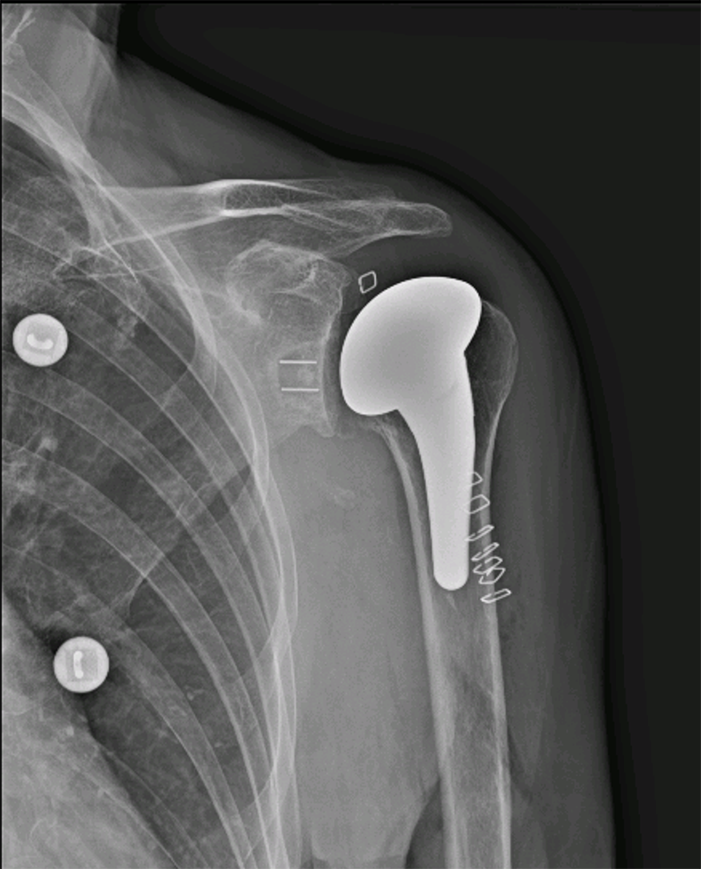

Prothèse d’épaule anatomique

Prothèse d’épaule anatomique, c'est quoi ?

L’objectif est de remplacer les surfaces articulaires usées, par des implants qui reproduisent l’anatomie de l’épaule. Pour pouvoir implanter ce type de prothèse, il faut que la coiffe des rotateurs soit intègre et que les dégâts osseux ne soient pas trop importants. Pour évaluer cela, votre chirurgien aura besoin d’un scanner pré-opératoire. Ce type de prothèse représente aujourd’hui environ 25% des prothèses d’épaule posées en France.

L’intervention se fait par une voie d’abord se situant à l’avant de l’épaule. L’abord de l’articulation nécessite une section du tendon du sous-scapulaire, qui sera réparé en fin d’intervention. Le chirurgien sectionne la tête humérale pour préparer l’os à l’aide de râpe et de compacteur pour positionner la tige humérale. Il prépare ensuite la glène de l’omoplate pour y implanter l’autre versant prothétique qui sera scellé dans l’os avec un ciment spécifique. Le chirurgien dispose de plusieurs tailles pour les implants qui sont adaptés à la morphologie de chaque patient. En fin d’intervention, le chirurgien positionnera un drain ou redon qui limitera la survenue d’un hématome post opératoire et qui sera retiré à 48 heures

Prothèse épaule anatomique - Dr Dumoulin​